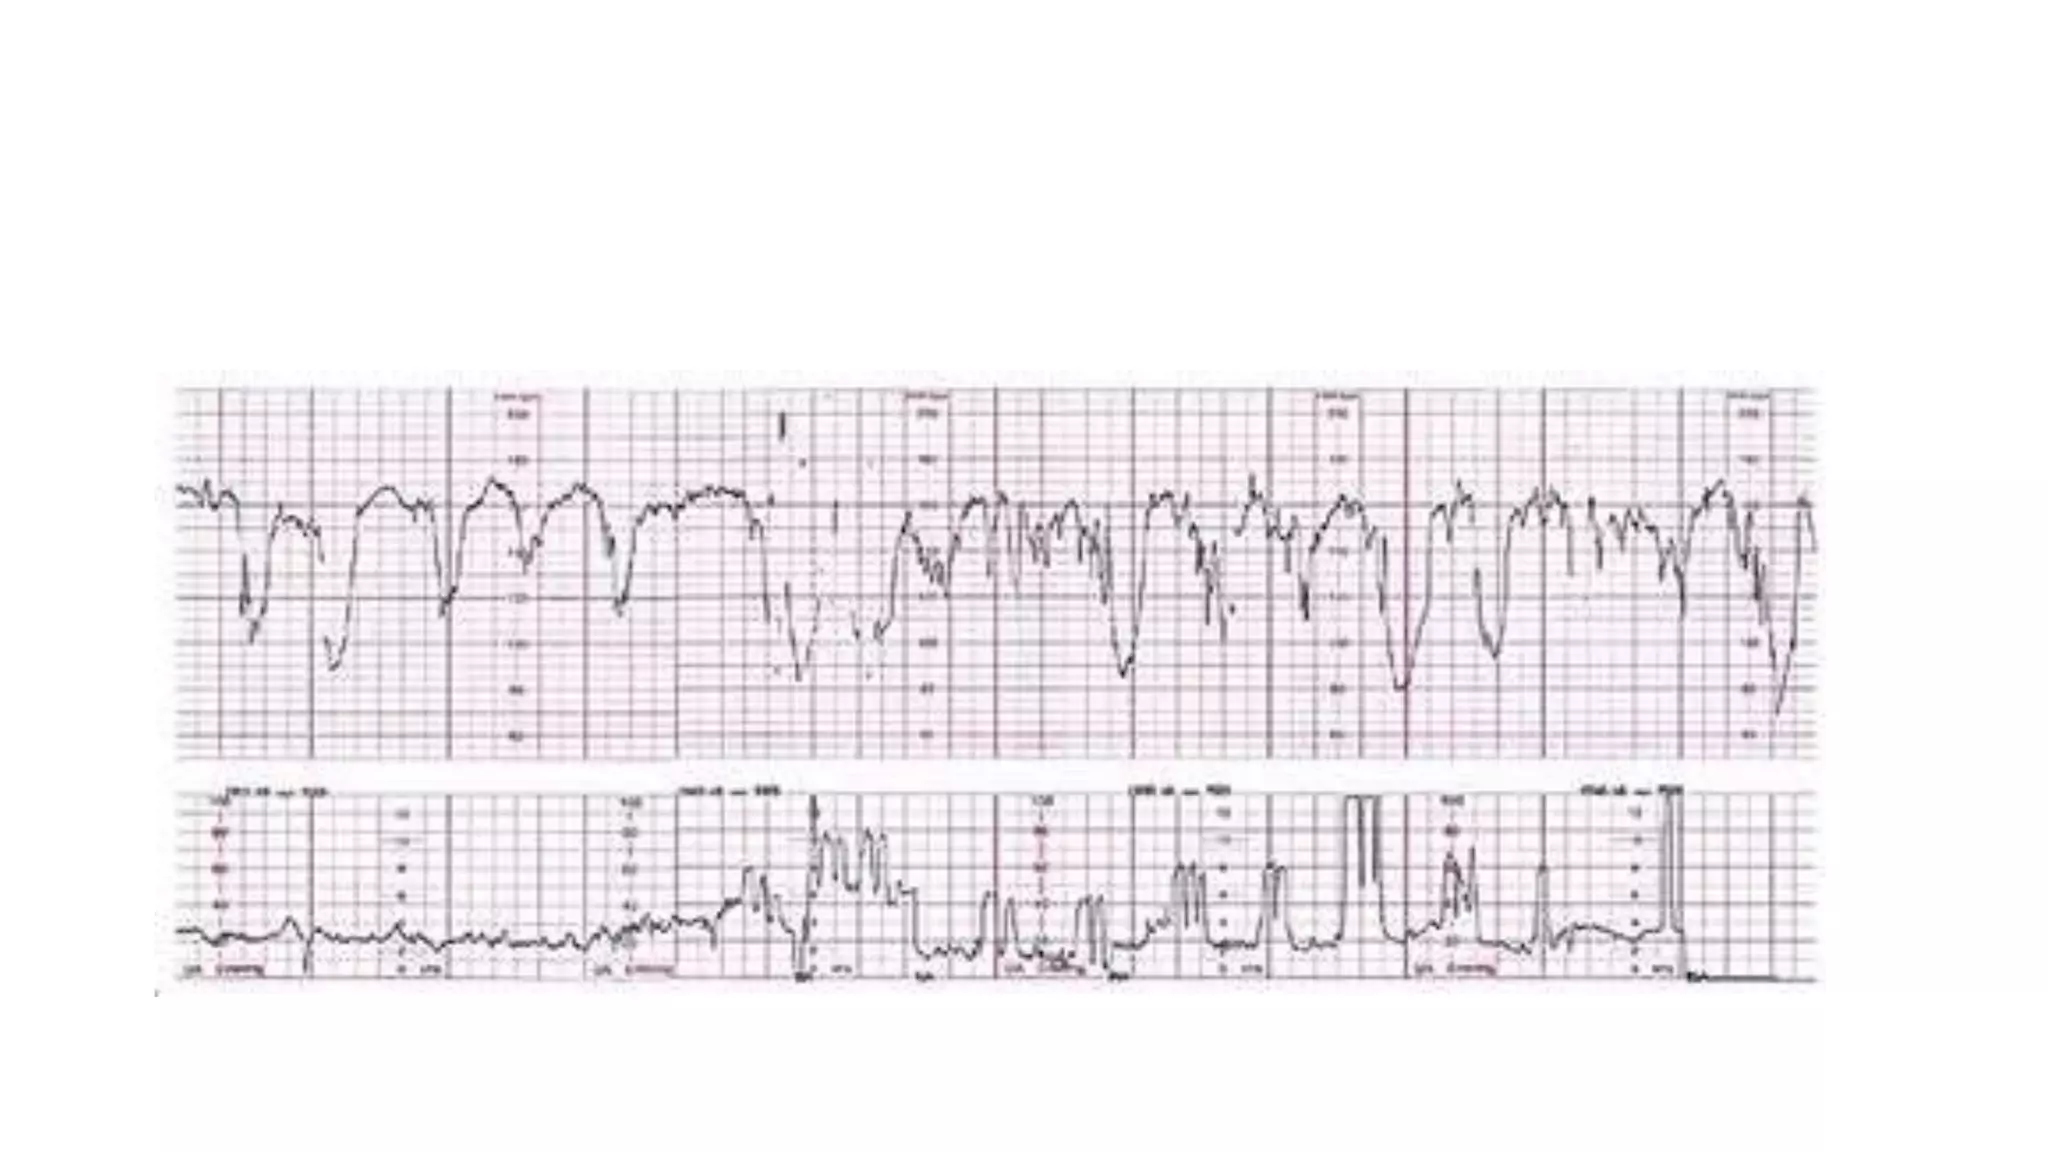

The document discusses key metrics for monitoring a baby's heart rate in utero, including the normal baseline rate of 100-160 bpm and variability. It also covers types of accelerations and decelerations that can occur, such as early or late, as well as bradycardia, which is an abnormally slow heart rate.